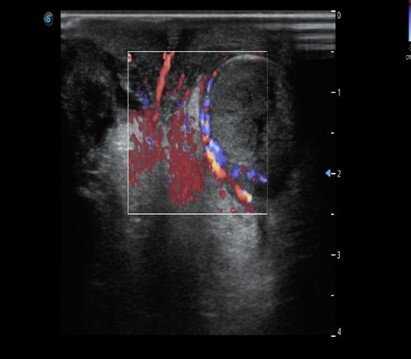

为求进一步治疗,康康至湖南省儿童医院急诊就诊,急复查彩超后以“左侧睾丸扭转”收入该院泌尿外科。该院在1小时内完成了所有的术前准备,并迅速安排手术团队为康康进行了急诊手术,可惜前期扭转时间长达30多小时,左侧睾丸已经因长时间缺血坏死,最终只能遗憾切除。